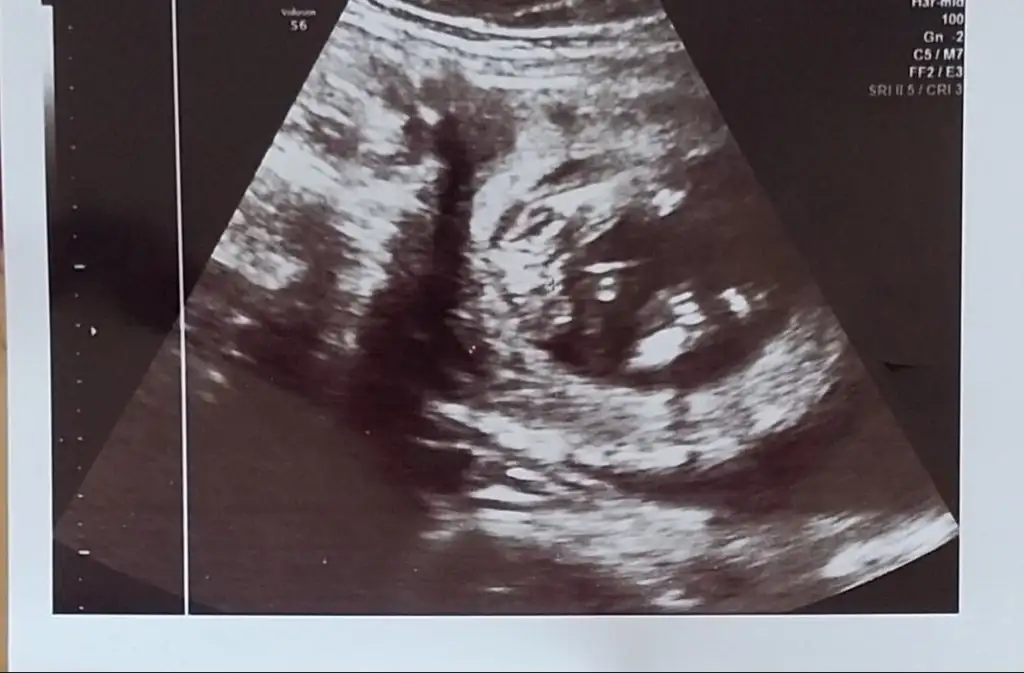

Merhaba banada tahmin yaparmisiniz

15 haftalikta dr. Kız cizgisi var kıza benziyor büyüsün biraz dedi ozaman kesinleşir sizde tahminde bulunurmusunuz?